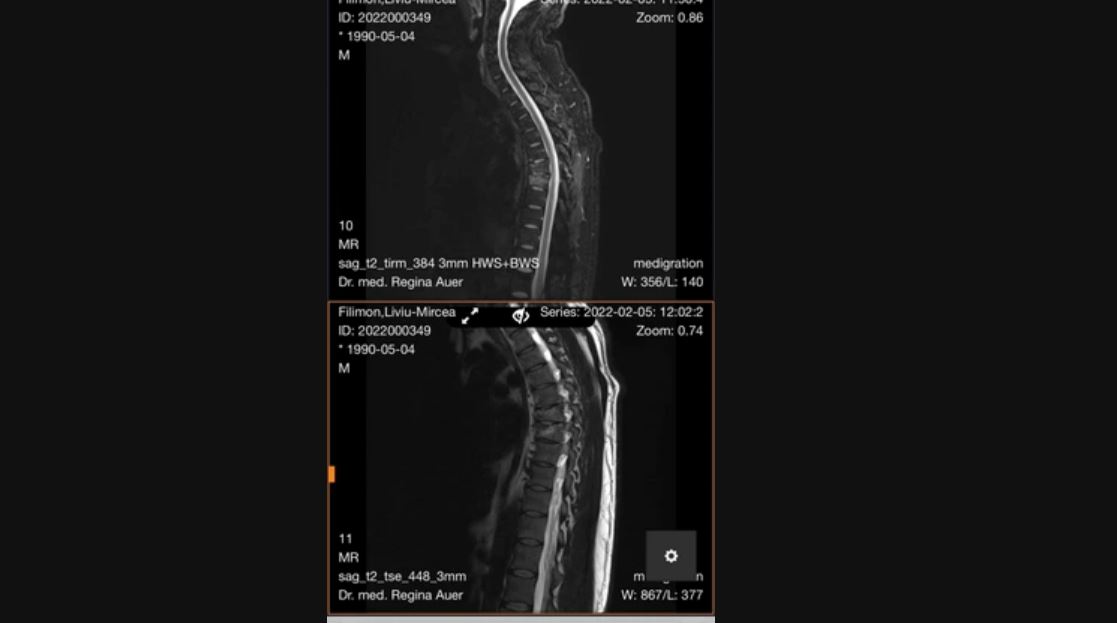

În urmă cu un an, una dintre cele mai frumoase seri din viața unui bărbat s-a transformat într-un calvar. Mai precis, Liviu, în vârstă de 32 de ani, a ajuns la spital de la propria nuntă, asta după ce invitații săi l-au aruncat în sus și l-au scăpat. La momentul respectiv, bărbatul s-a lovit foarte tare la spate, iar în prezent, Liviu este extrem de deranjat de faptul că prietenii lui nici măcar nu l-au contactat pentru a-l întrebat cum se simte.

Fericitul eveniment a avut loc pe data de 19 septembrie 2021, la Băile Felix, însă întreaga bucuria a mirilor s-a umbrit de îndată ce Liviu a fost luat pe sus de către 4 nuntași, apoi aruncat de câteva ori în aer. Din nefericire, ultima aruncare l-a trimis pe Liviu direct la spital, acesta lovindu-se foarte tare la spate.

„Am stat cam patru săptămâni în spital, în Germania, și după aceea am stat la pat două săptămâni, acasă, fără să mă pot ridica. Au urmat două luni în care mi s-a permis să mă ridic din pat, dar nu mai mult de 10 minute. Abia după 7-8 luni de tratamente și recuperare am putut să reîncep lucrul. Dar și așa, din cauza durerilor pe care le am la spate, nu pot lucra mai mult de 4 ore pe zi”, a  povestit acesta pentru presa locală.

„Ei au râs şi s-au distrat. Dar eu am şi acum probleme şi s-ar putea să am nevoie de o operaţie. Am două vertebre fracturate din cauza acelei glume. Mi-au stricat nunta, la serviciu nu dau acelaşi randament, pentru că am dureri, nu pot să-mi ridic fetiţa de 4 kilograme în braţe, nu pot face nimic”, a mai declarat bărbatul, pentru Adevărul.